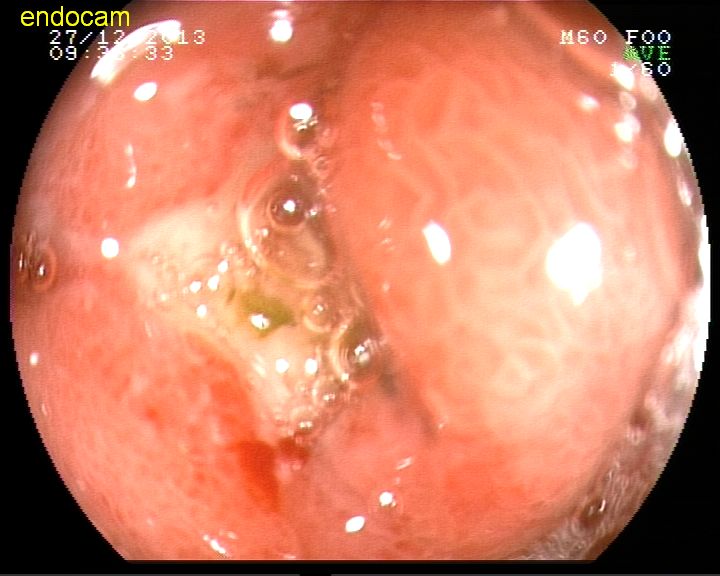

Mide ülseri